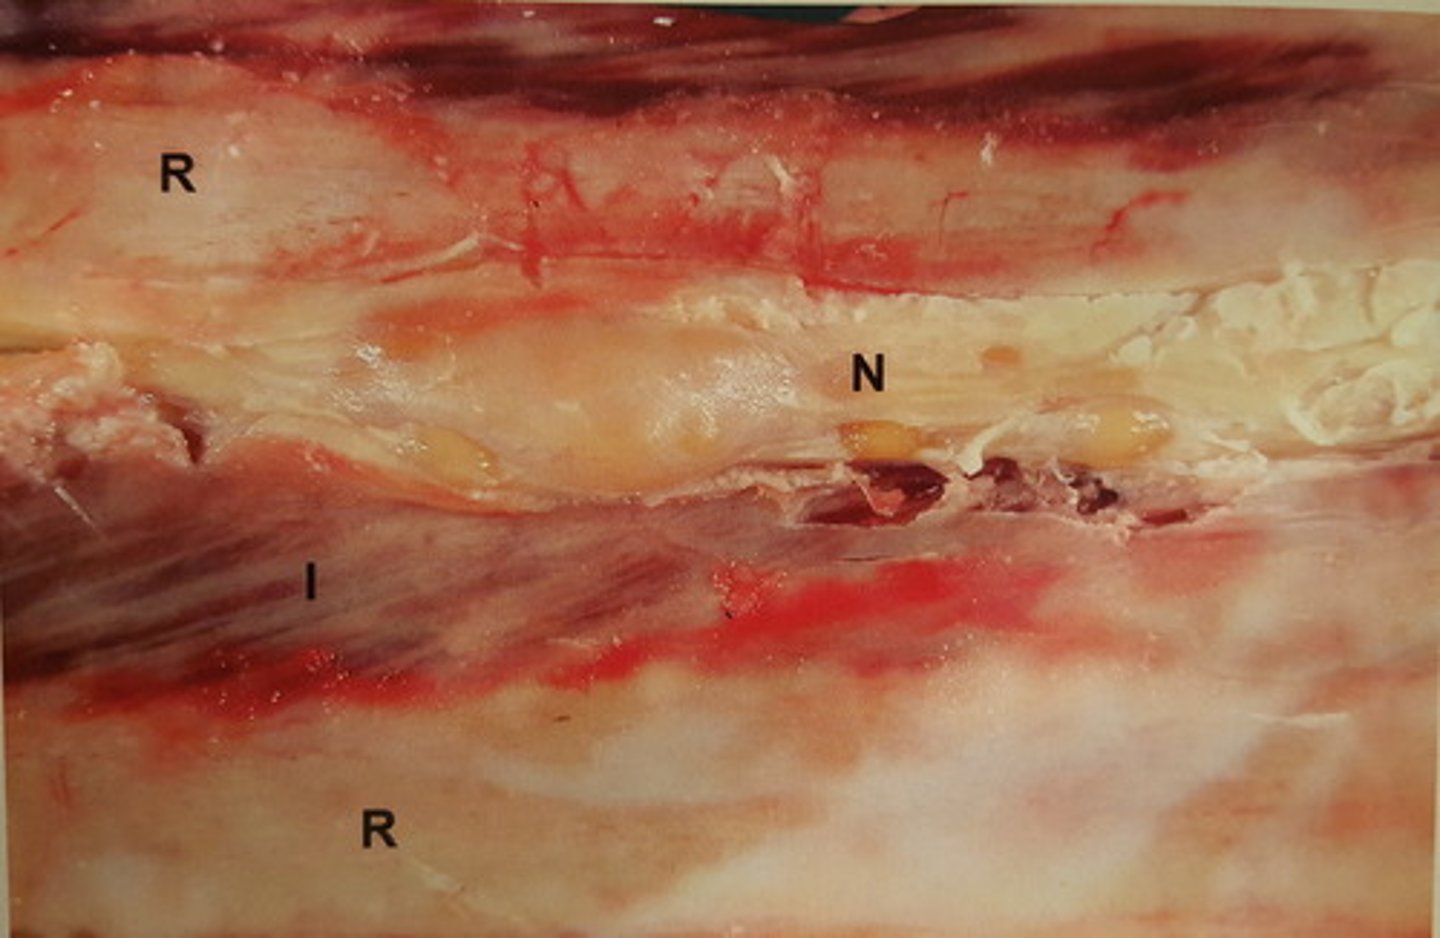

multiple Schwannomer

Intercostalnerver hos okse. Patoanatomisk diagnose?

R=ribben, N=nerver, I=muskulatur